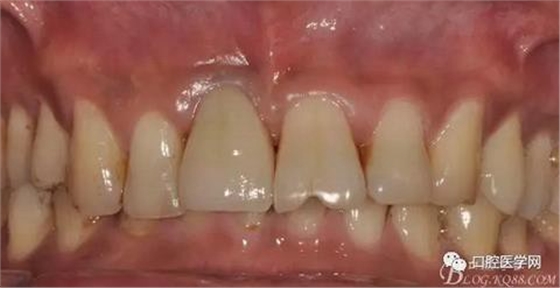

圖4 術(shù)前正位頜面照

圖21 術(shù)后正位照

圖22 術(shù)后正位黑背板照

圖23 術(shù)后正位咬頜照